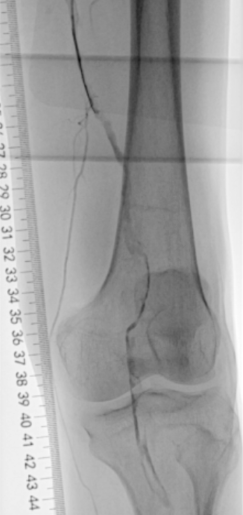

▲腘动脉可见充盈缺损

▲膝下主干动脉未见显影

2.使用Rotarex导管由近至远进行血栓抽吸,少量血栓残留,置入溶栓管溶栓。

▲血栓清除后管腔获得较满意,仍有少量残留血栓